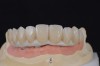

Fig 6. All-acrylic provisional prosthesis on the temporary cylinders.

Figure 6